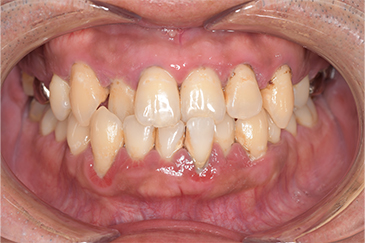

CASE 2

Before

After

基本情報

| 年齢・性別 | 30代・男性 |

| 主訴 | 歯石を取りたい |

| 治療内容 | 超音波スケーラーでの歯石除去 |

| 治療期間 | 60分 |

| 治療費 | 初診料を含め約4,500円 |

| リスク・副作用 | 歯ぐきに違和感や痛みを覚える場合がある。 1週間程度、歯を磨くといつもより出血することがある。 腫れていた歯ぐきが引き締まることで歯ぐきが下がった様に見える。 歯ぐきが下がることで歯がみしやすくなることがある。 一時的に歯の動揺(ゆれ)が増す場合がある。 |